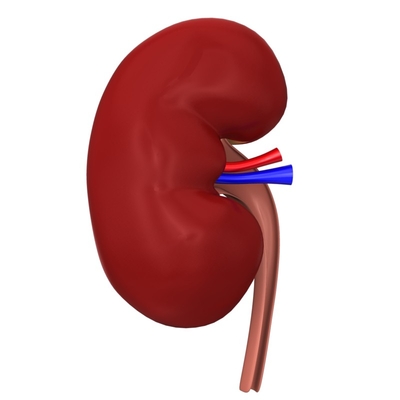

Строение почек человека: Фото и описание